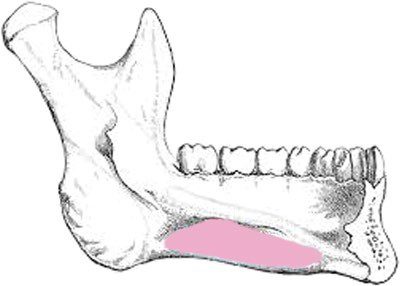

Hố dưới hàm

Hố dưới hàm là khoang ở hai bên, nằm ở phía trong thân xương hàm dưới và bên dưới đường hàm móng.

Hố dưới hàm chứa tuyến nước bọt dưới hàm, tạo ra 65% đến 70% nước bọt. Chân răng khôn thường nằm gần với hố dưới hàm.

Vỏ xương phía lưỡi ở khu vực này có thể mỏng hoặc mất hoàn toàn. Do đó, lực quá mức hoặc đặt sai vị trí có thể làm bật các mảnh chân răng hoặc thậm chí toàn bộ răng vào hố dưới hàm gần đó.